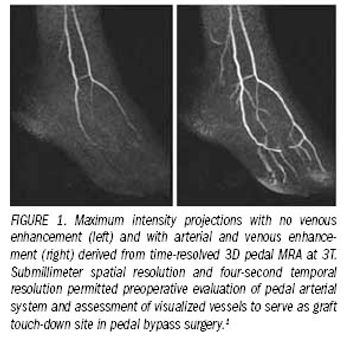

Cardiovascular MR imaging has become a valuable diagnostic modality.